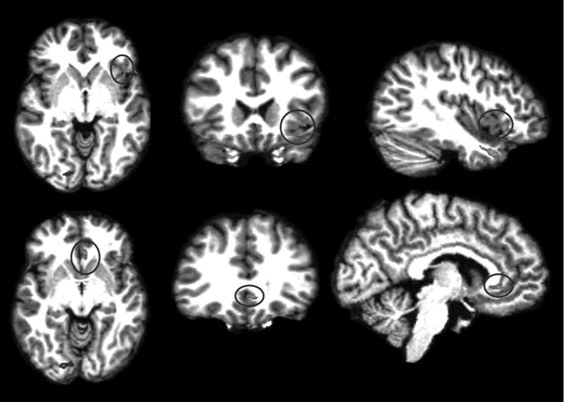

Анализируя далее научную литературу, мы пришли к выводу, что процесс поведенческого подражания с участием верхних отделов височной коры и эмоциональный (физиологический) резонанс, требующий участия островка, тоже имеют отношение к системе зеркальных нейронов. При подражании верхние отделы височной коры кодируют сложные процессы сенсорных следствий двигательных актов; при эмоциональном резонансе островок осуществляет физиологический и аффективный сдвиг, имитирующий его у другого человека. Исходя из параллелизма этих функций реципрокного действия (имитационной, физиологической и аффективной), мы можем использовать термин «резонансный контур», подразумевая, что в нем могут участвовать зеркальные нейроны, но не все компоненты этого контура двигательные, поэтому формально мы не можем назвать такой контур зеркальным. В нашем обсуждении мы примем во внимание это отличие и будем называть резонансный контур именно так, или будем прибегать к выражению «области, связанные с системой зеркальных нейронов» (рис. П.1 и П.2).

П.1

П.2

Рис. П.1, П.2. Функциональная МРТ, выполненная во время выполнения медитации осознавания дыхания. На снимках видна активация верхней височной извилины (рис. П.1) и активация островка и вентрального отдела передней поясной извилины (рис. П.2). Верхняя височная кора, островок и области срединной префронтальной коры (показанные здесь) вместе с системой зеркальных нейронов, как предполагается в тексте, содержат элементы «резонансного контура», которые активируются в ходе внимательного осознавания (снимки напечатаны с разрешения Сары Лазар © 2005)